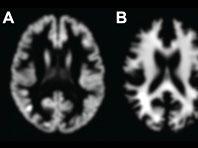

Новый метод поможет определить риск преждевременной смерти

Ученые из Имперского колледжа Лондона использовали МРТ и машинное обучение. Специалисты научили компьютер вычислять возраст мозга людей по объему их мозговой ткани. Потом исследователи оценивали, соответствовал ли реальный возраст людей возрасту их мозга,...